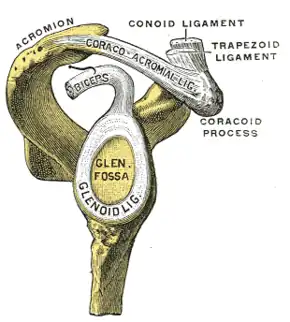

| The glenoid labrum, labeled glenoid ligament, is damaged in a Bankart lesion. Lateral view demonstrating the articular surface of the right scapula is shown. | |